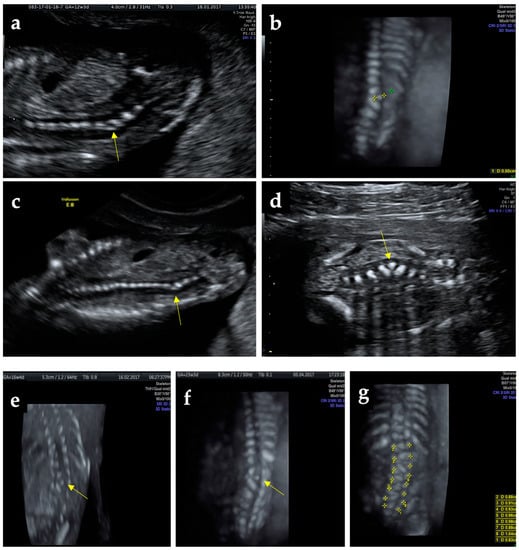

A 26-year-old pregnant woman with no history of previous births and a spontaneous, uncomplicated abortion at 6 weeks of gestation presents for pregnancy monitoring at 5 weeks of gestation. Family medical history was insignificant. The pregnancy uneventfully evolves through prescribed medication (prenatal vitamins and low dose aspirin 75 mg/day) without folic acid pre-conception prophylaxis. At 12 weeks of gestation during first-trimester screening, combining ultrasound and biochemical test, on ultrasonography (performed with a Voluson E8 machine system from GE Healthcare, Chicago, Illinois, USA, equipped with a transabdominal RAB6-RS convex probe and a RIC5-9-D transvaginal probe), nuchal translucency was in the normal range (1.60 mm), the pulsatility index of ductus venosus was 0.84, nasal bone was present, normal activity and structure of the fetal heart were also normal, and a crown–rump length of 65.6 mm corresponding to 12 weeks and 6 days of gestation was measured. In the coronal plane, at the L3–L4 spine level, there was observed a triangular hyperechoic structure on the lateral side of the spinous processes, located between vertebrae normally positioned and determining a sharp angulation of the column spine with the concavity to the left (Figure 1a–d); all the other scanning planes (sagittal and transverse) appeared normal. Repeated ultrasound examinations at 16, 17, and 23-weeks using Tomographic Ultrasound Imaging (TUI) and three-dimensional (3D) reconstruction during pregnancy revealed no progress of angulation, with no lordosis or scoliosis and without any adjacent aspect suggestive of a neural tube defect (Figure 1e–i and Supplementary Video S1). A careful morphologic inspection did not find other associated malformations. The suspected diagnosis of supernumerary hemivertebra was confirmed at that stage of the pregnancy by two other ultrasonography specialists. The combined test at 12 weeks and 6 days of gestation placed the patient in the low-risk group for chromosomal anomalies. Because the patient could not afford an additional test, the fetal karyotype was not performed. After counseling regarding the possible complications and associated anomalies, the future parents opted for the continuation of pregnancy.

Figure 1.

Ultrasound findings: (a) suspect angulation of the thoracolumbar spine at 12-weeks show the hemivertebrae (yellow arrow), (b) zoom-in above the hemivertebrae in 3D static reconstruction, (c) image of the whole spine at 12-weeks; (d) clear 2D imaging of the hemivertebrae; (e,f)—US scans of the fetal spine at 16 and 23 weeks, (g) tracing the correspondence of the vertebrae lateral ossification centers, (h) numbering and positioning of the vertebrae at 23 weeks on 2D ultrasound sepia mode, (i) Tomographic Ultrasound Imaging (TUI)—successive scans of the spine revealing the anomaly.